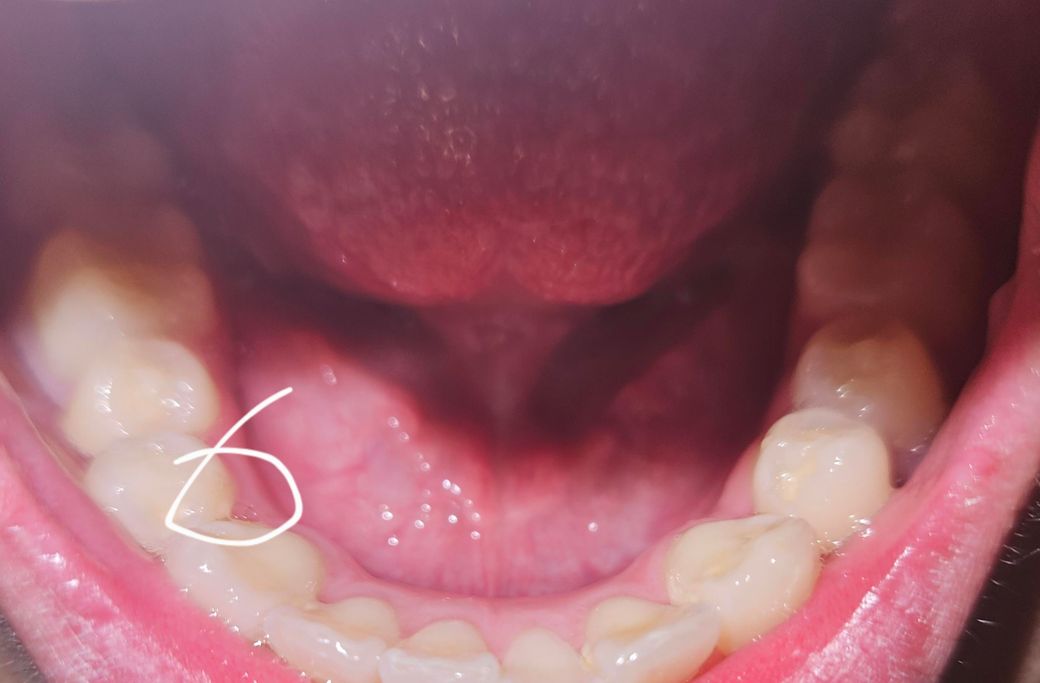

이빨 안쪽 사이에 날카롭게 베입니다. 치과를 가도 날카로운게 없다는데 이게 진짜 뭔가여?

이빨 안쪽 사이에 매일같이 베입니다.

도대체 이건 뭔가여... 이거 땜에 날카롭게 혀가 베여서 치과 간게 한두번이 아닌데 원인도 못찾고 다른 병원에선 치석이 쌓였다고 하고, 다른곳은 치석이 날카롭지 않다고 하고, 스케일링 괜히 한거 같아서 진짜 서글픕니다.

• 1번 째 사진

제가 사진으로 보기에는 치석이 맞는 것 같아요. 다른 곳에도 치석이 조금씩 끼어있고 그 부분과 색과 같아보입니다. 이전에도 스케일링 후에는 괜찮은데 한달정도 지나면 또 날카로워진다고 질문글 올리셨던걸로 기억합니다. 제 생각에는 스케일링 후에는 치석이 있던 자리가 비어서 그 틈새에 혀도 일부분 들어가는데 그 자리에 조금씩 치석이 끼면서 그게 날카롭게 느껴지시는 것 같습니다. 스케일링 받으신지 얼마 안되었는데 다른 부분에도 전체적으로 사이사이 치석이 있는 것을 보면 양치가 조금 덜 되시는 것 같아요. 한번 더 치아틈새에 깨끗하게 치석제거 받으시고 치실을 매일 사용해보세요. 그러면 치석이 끼이지 않아요.

사진상 봤을때는 이물질, 치석 같아보입니다 대학병원 치주과가서 체크해보시기 바랍니다

잇몸이 내려가면서 치근이 노출되어 이로인해 날카롭게 느껴질수 있습니다. 부드러운 칫솔과 올바른 양치법으로 잇몸을 관리하길 권하며, 필요시에 진료를 받고 잇몸 이식이 가능합니다.

또한 치석이 치아 사이에 쌓이거나 음식물 찌꺼기가 치아 틈에 끼어 단단해진 경우 날카롭게 느껴질 수 있습니다.